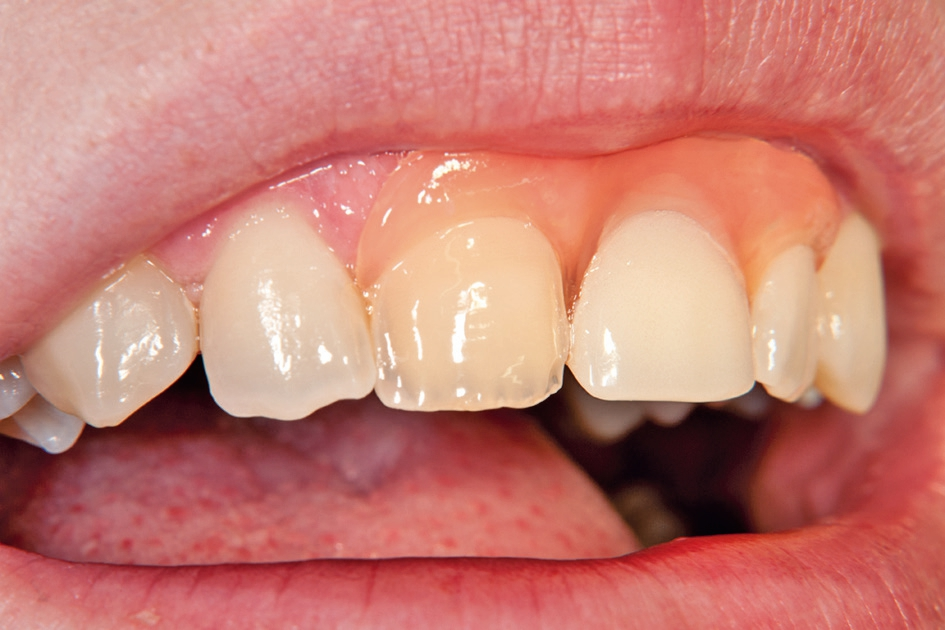

Gleichzeitig mit der prothetischen Versorgung des Implantats wurde auch für Zahn 11 ein Veneer geplant. Zum Einsatz kam ein Zeramex T Implantat Durchmesser 5,5 mm, Länge 12 mm. Für die Kronenversorgung wurde ein mit e. Max überpresstes CAD-Abutment gewählt. Während der Einheilphase des Implantats kam eine Sunflex-Prothese zum Einsatz.